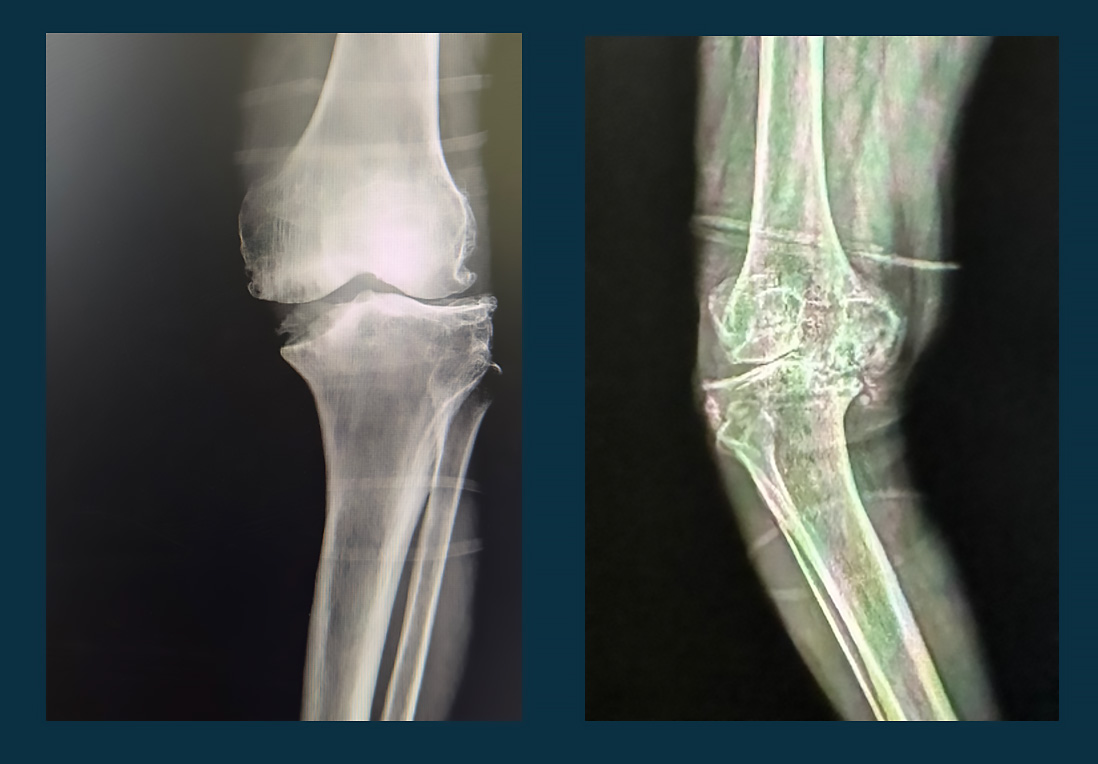

(DİZ EKLEMİ OSTEOARTRİTİ)

Gonartroz, diz eklemindeki kıkırdak dokusunun zamanla aşınması ve dejenerasyonu sonucu ortaya çıkan bir tür eklem hastalığıdır. Bu durum genellikle yaşlanma süreciyle ilişkilidir, ancak bazen genetik faktörler, aşırı kilo, eklem travmaları veya belirli meslekler gibi diğer faktörler de etkili olabilir. Gonartroz, diz ekleminde ağrı, şişlik, sertlik ve hareket kısıtlılığı gibi belirtilerle kendini gösterir.